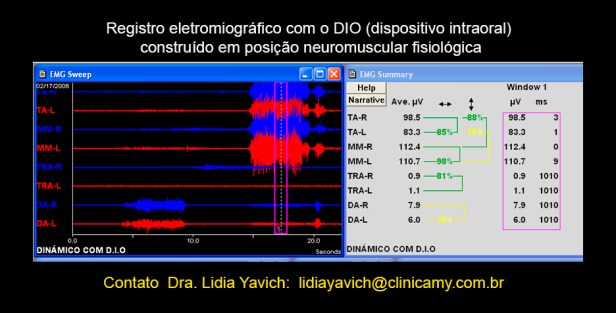

Registro eletromiográfico do paciente em oclusão neuromuscular fisiológica com o dispositivo em boca: os temporais anteriores direito e esquerdo estão equilibrados.

O registro inicial em oclusão habitual registrava quase 70 por cento de diferencia entre o temporal esquerdo e o direito em oclusão máxima habitual.

Registros eletromiográficos comparativos: o superior em oclusão habitual e o inferior em oclusão neuromuscular fisiológica com o DIO (dispositivo intraoral) em boca.

O DIO (dispositivo intraoral) é planejado não só pela desprogramação eletrônica, mas também pelas imagens e outros auxiliares do diagnóstico. É controlado, trocado e recalibrado como parte de um tratamento.

O DIO deve ser mensurado eletromigráficamente. Logicamente a melhoria da sintomatologia do paciente deve acompanhar a melhoria dos registros.